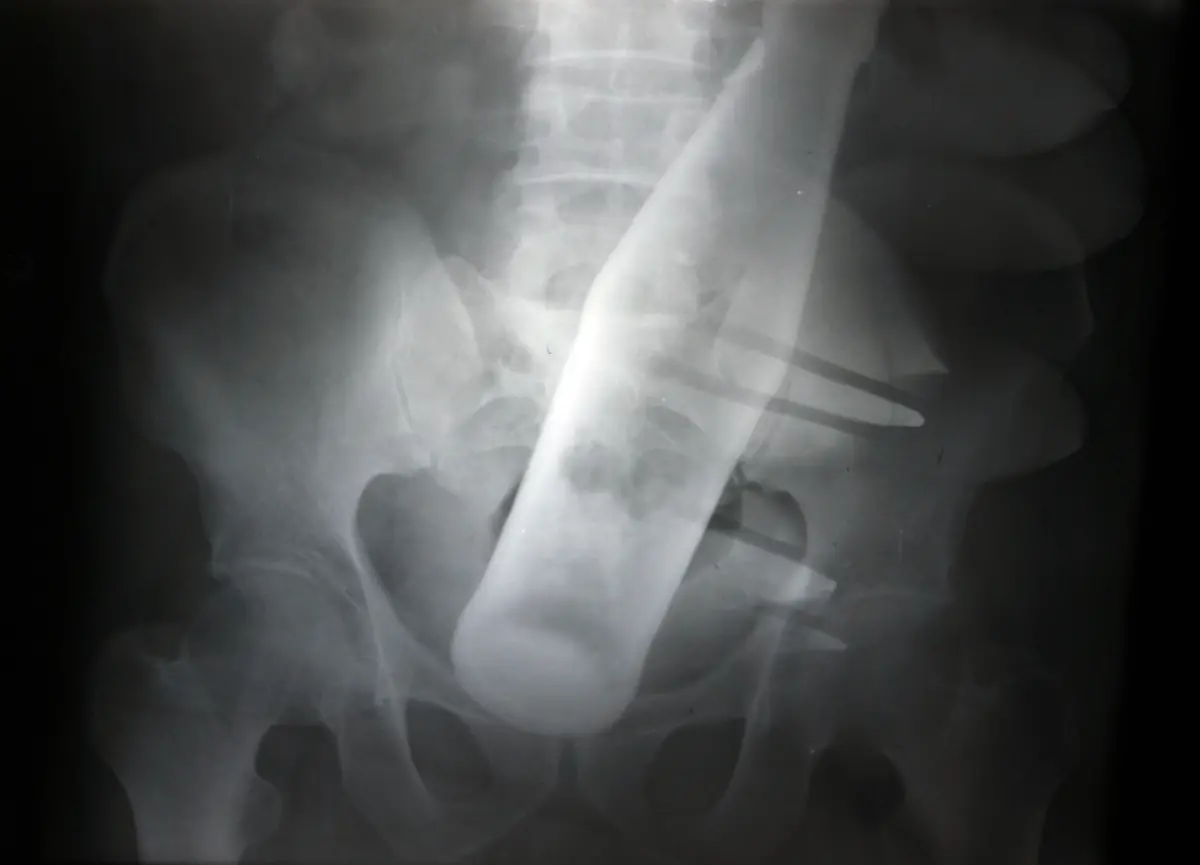

Nägel, Messer, TelefoneWas Röntgenstrahlen zum Vorschein bringen

Nicht immer zeigen Röntgenaufnahmen das, was man von ihnen erwartet. Oft kommt es zu Bildern, die selbst hartgesottene Betrachter zum Schaudern bringen - und der Wissenschaft Rätsel aufgeben.